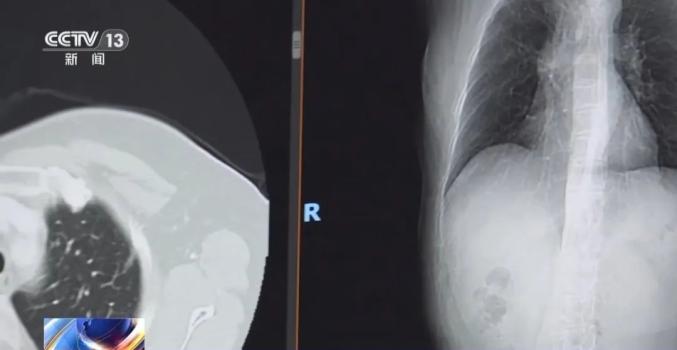

在宁波山区,80多岁的陈老婆(化姓)过着简单健康的生活:平时做农事,做家务,不沾烟不沾酒,远离环境污染...然而,一次体检打破了平静——胸部CT显示陈老婆左肺有磨玻璃结节,术后被诊断为肺腺癌。

更令人震惊的是,陈阿婆确诊后,她的三个女儿也在筛查中被诊断为肺癌,其中两个是肺腺癌,一个是肉瘤样癌。最后,他们都接受了手术。四个母女想不通的是,她们没有吸烟史,生长环境干净。他们怎么能直接被肺癌发现?

专家指出,大多数筛查中发现的磨玻璃样小结节都需要仔细解读。它生长非常缓慢,可以在一定的冷静期观察,不建议过度治疗。

伴随着我国医学的进步,肺癌病人的治疗取得了显著突破,肺癌磨玻璃样结节,~10年生存率接近100%,实性硬块一期肺癌5年生存率约为70%~80%。